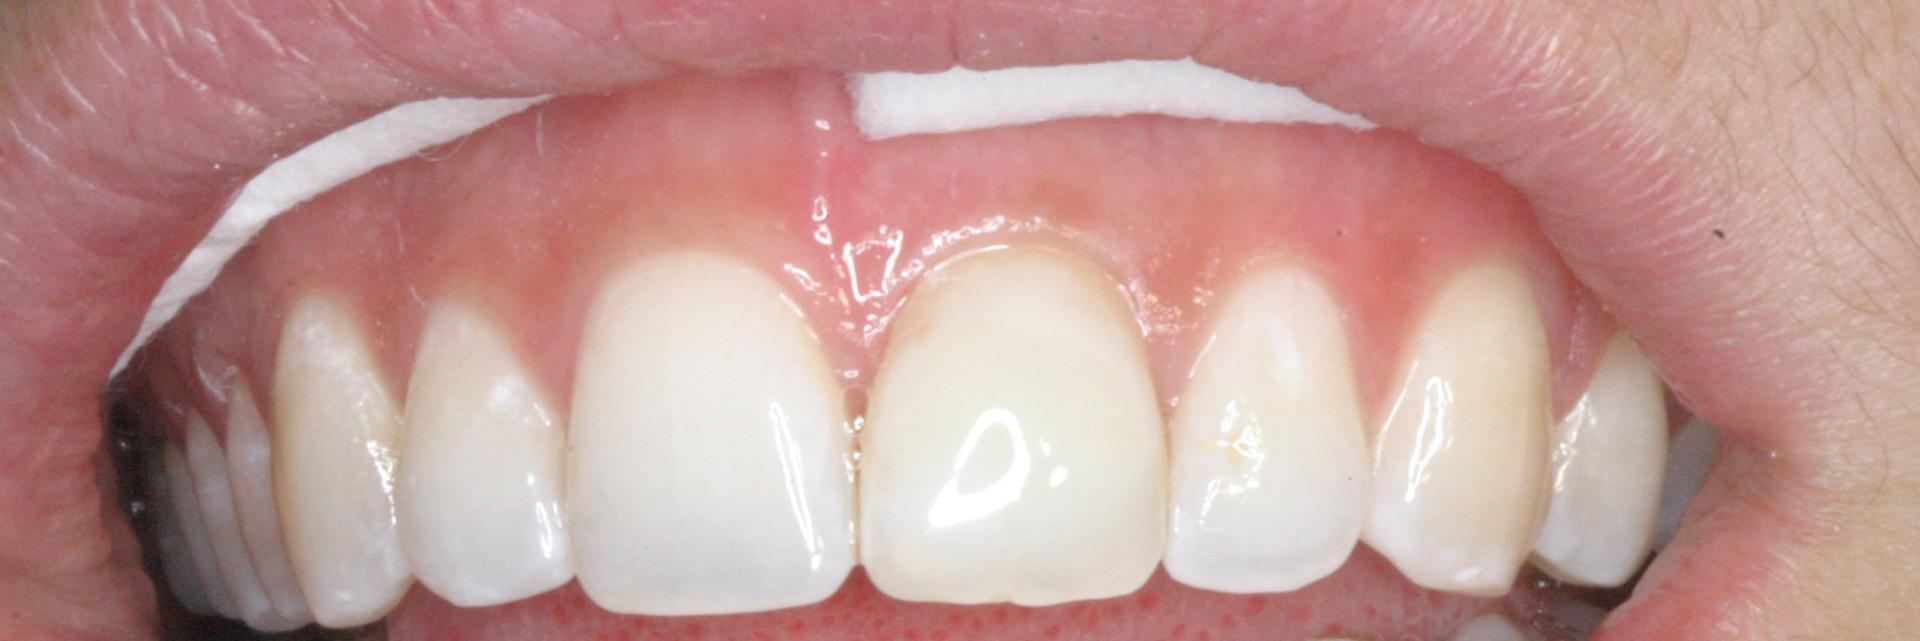

Discoloration due à un traitement de racine

Après 1 mois et 2 séances de blanchiment interne